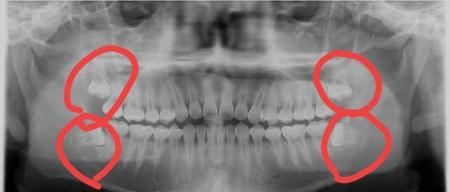

有龋齿或者其它口腔牙周问题去看牙医,也可以自己注意一下检查时拍的x光片。

数一数看到的牙根,如果牙列超过28颗,那就是有智齿。

即使智齿还没有开始长,藏在牙骨里,一样能看到牙胚。